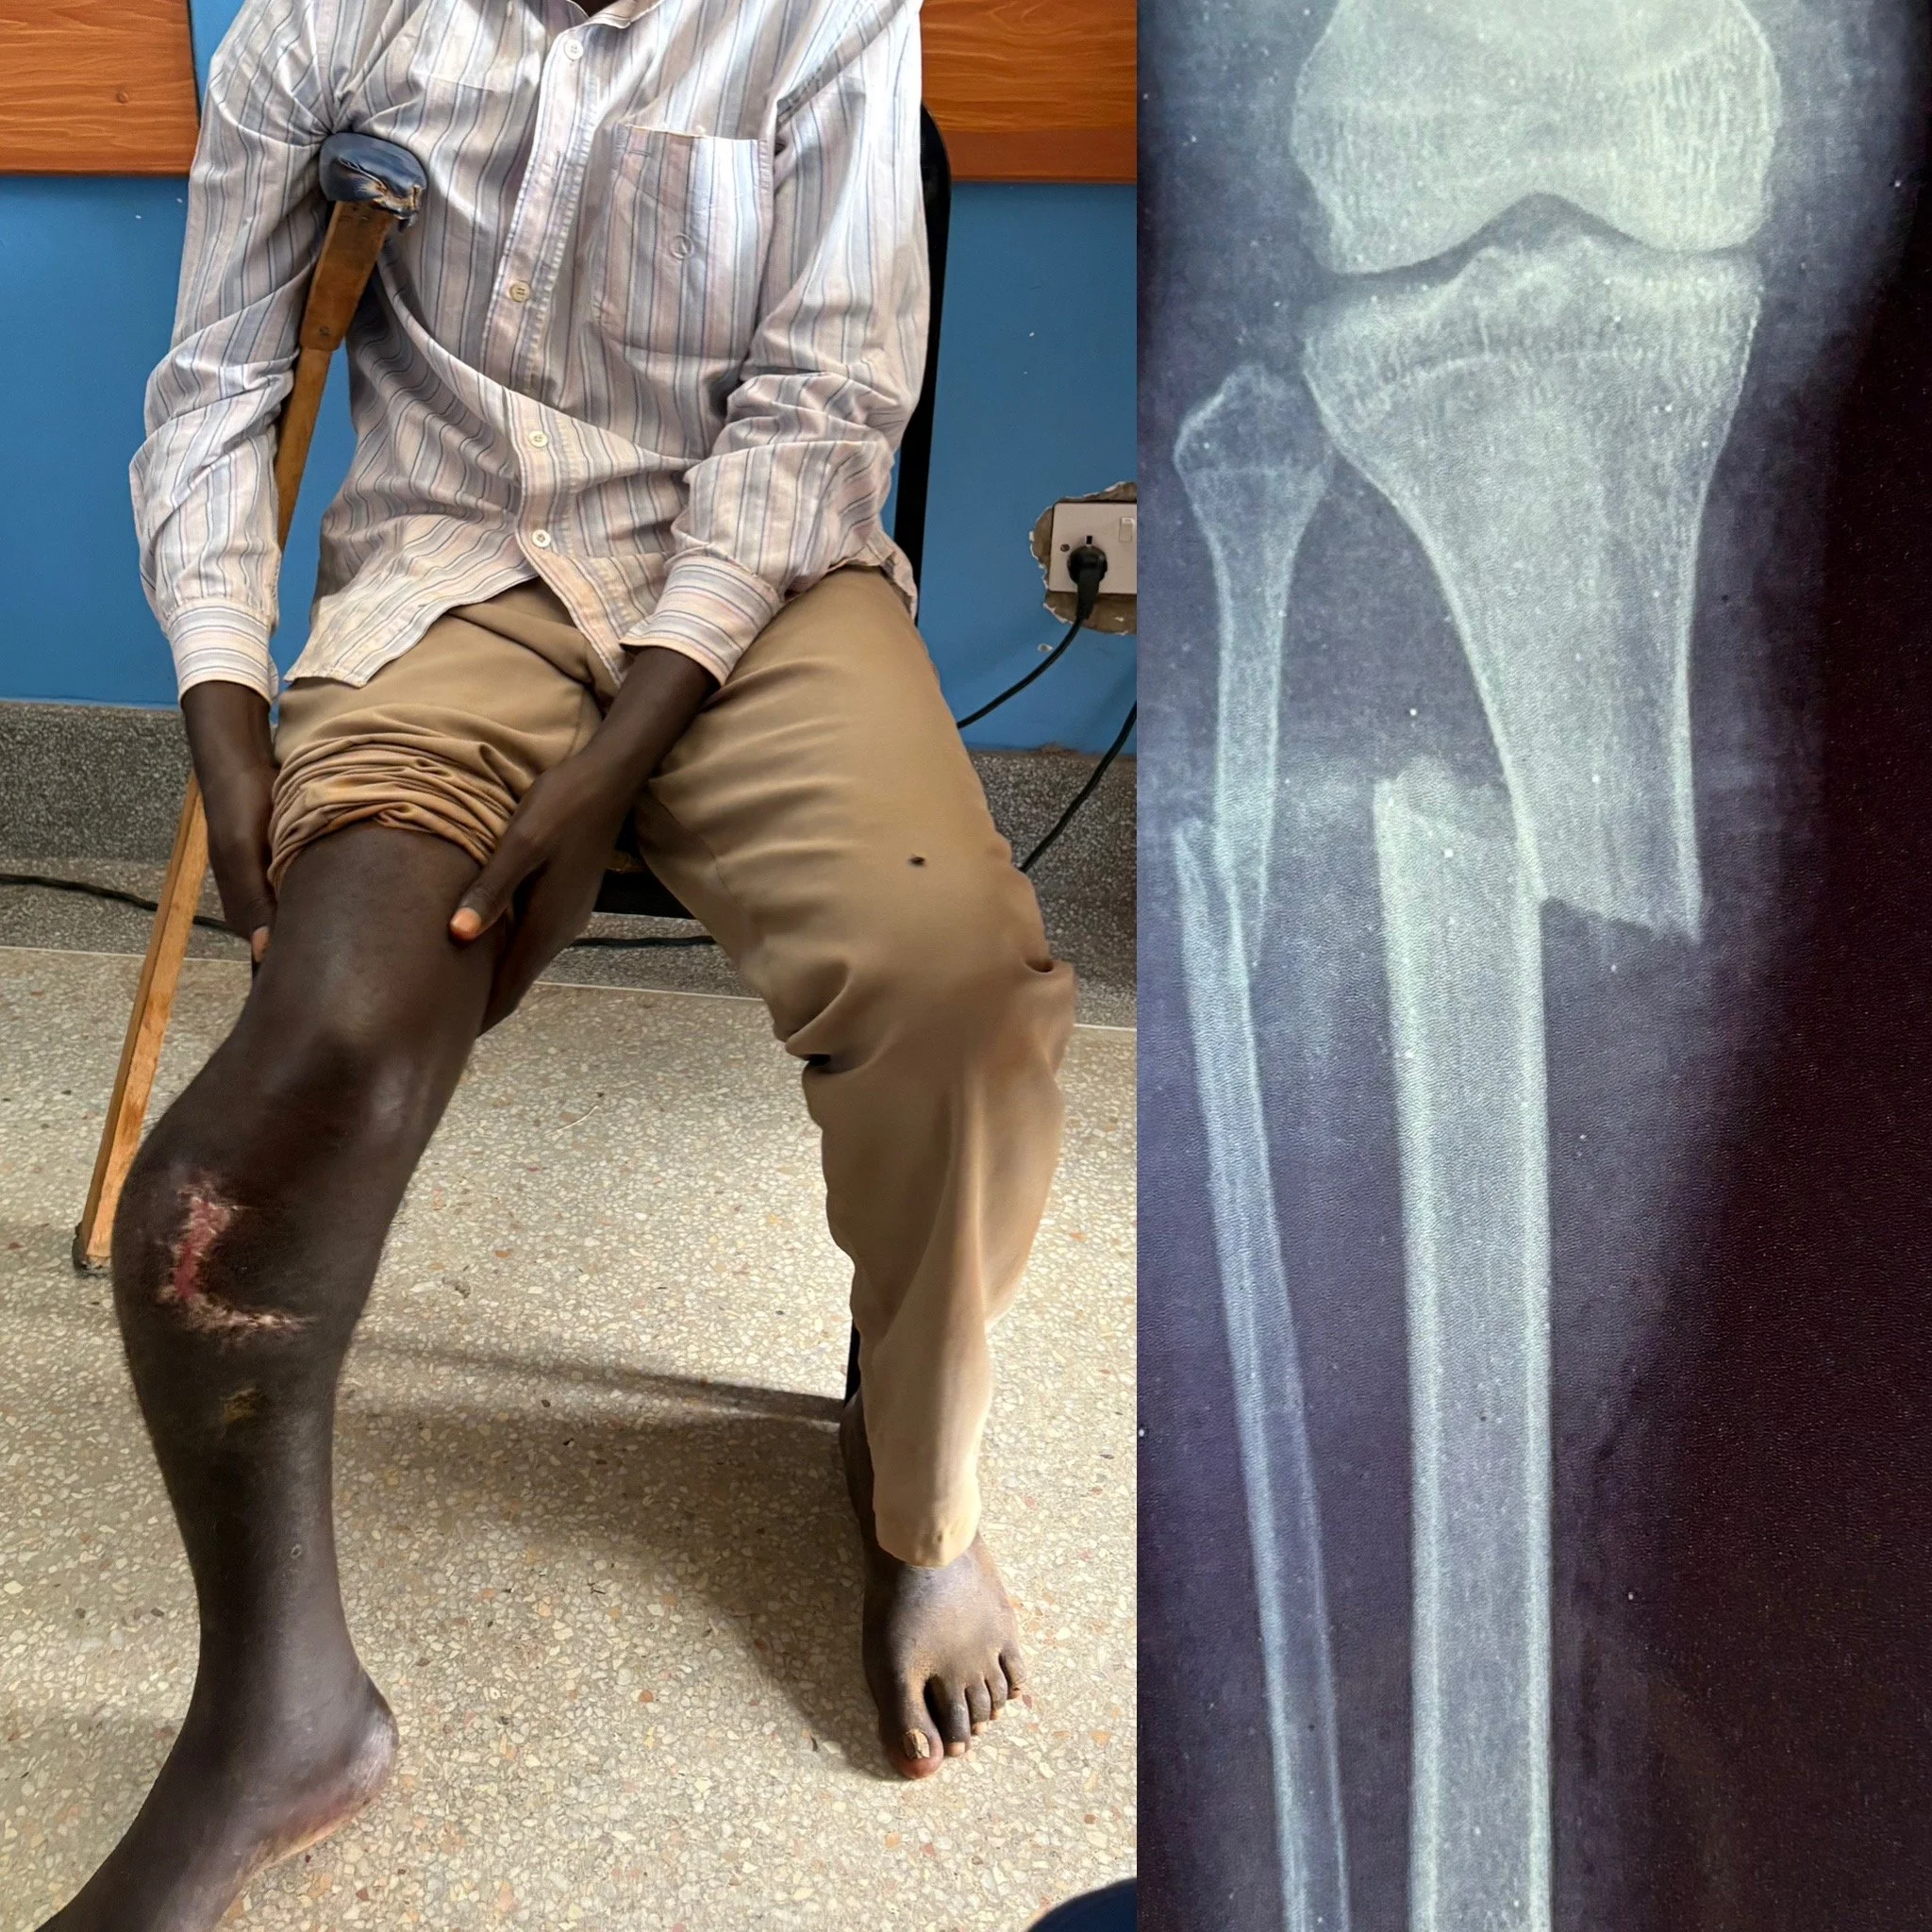

We are incredibly grateful and excited to welcome Dr. Miller to Uganda, where he is providing life-changing orthopedic care to those in need. As a highly experienced orthopedic surgeon, Dr. Miller specializes in treating bone and joint disorders, offering surgeries that restore mobility, reduce chronic pain, and help individuals regain independence.

Countless people in Uganda suffer from orthopedic conditions that limit their ability to walk, work, and care for themselves. With Dr. Miller’s expertise, patients will receive critical surgical interventions that dramatically improve their quality of life.